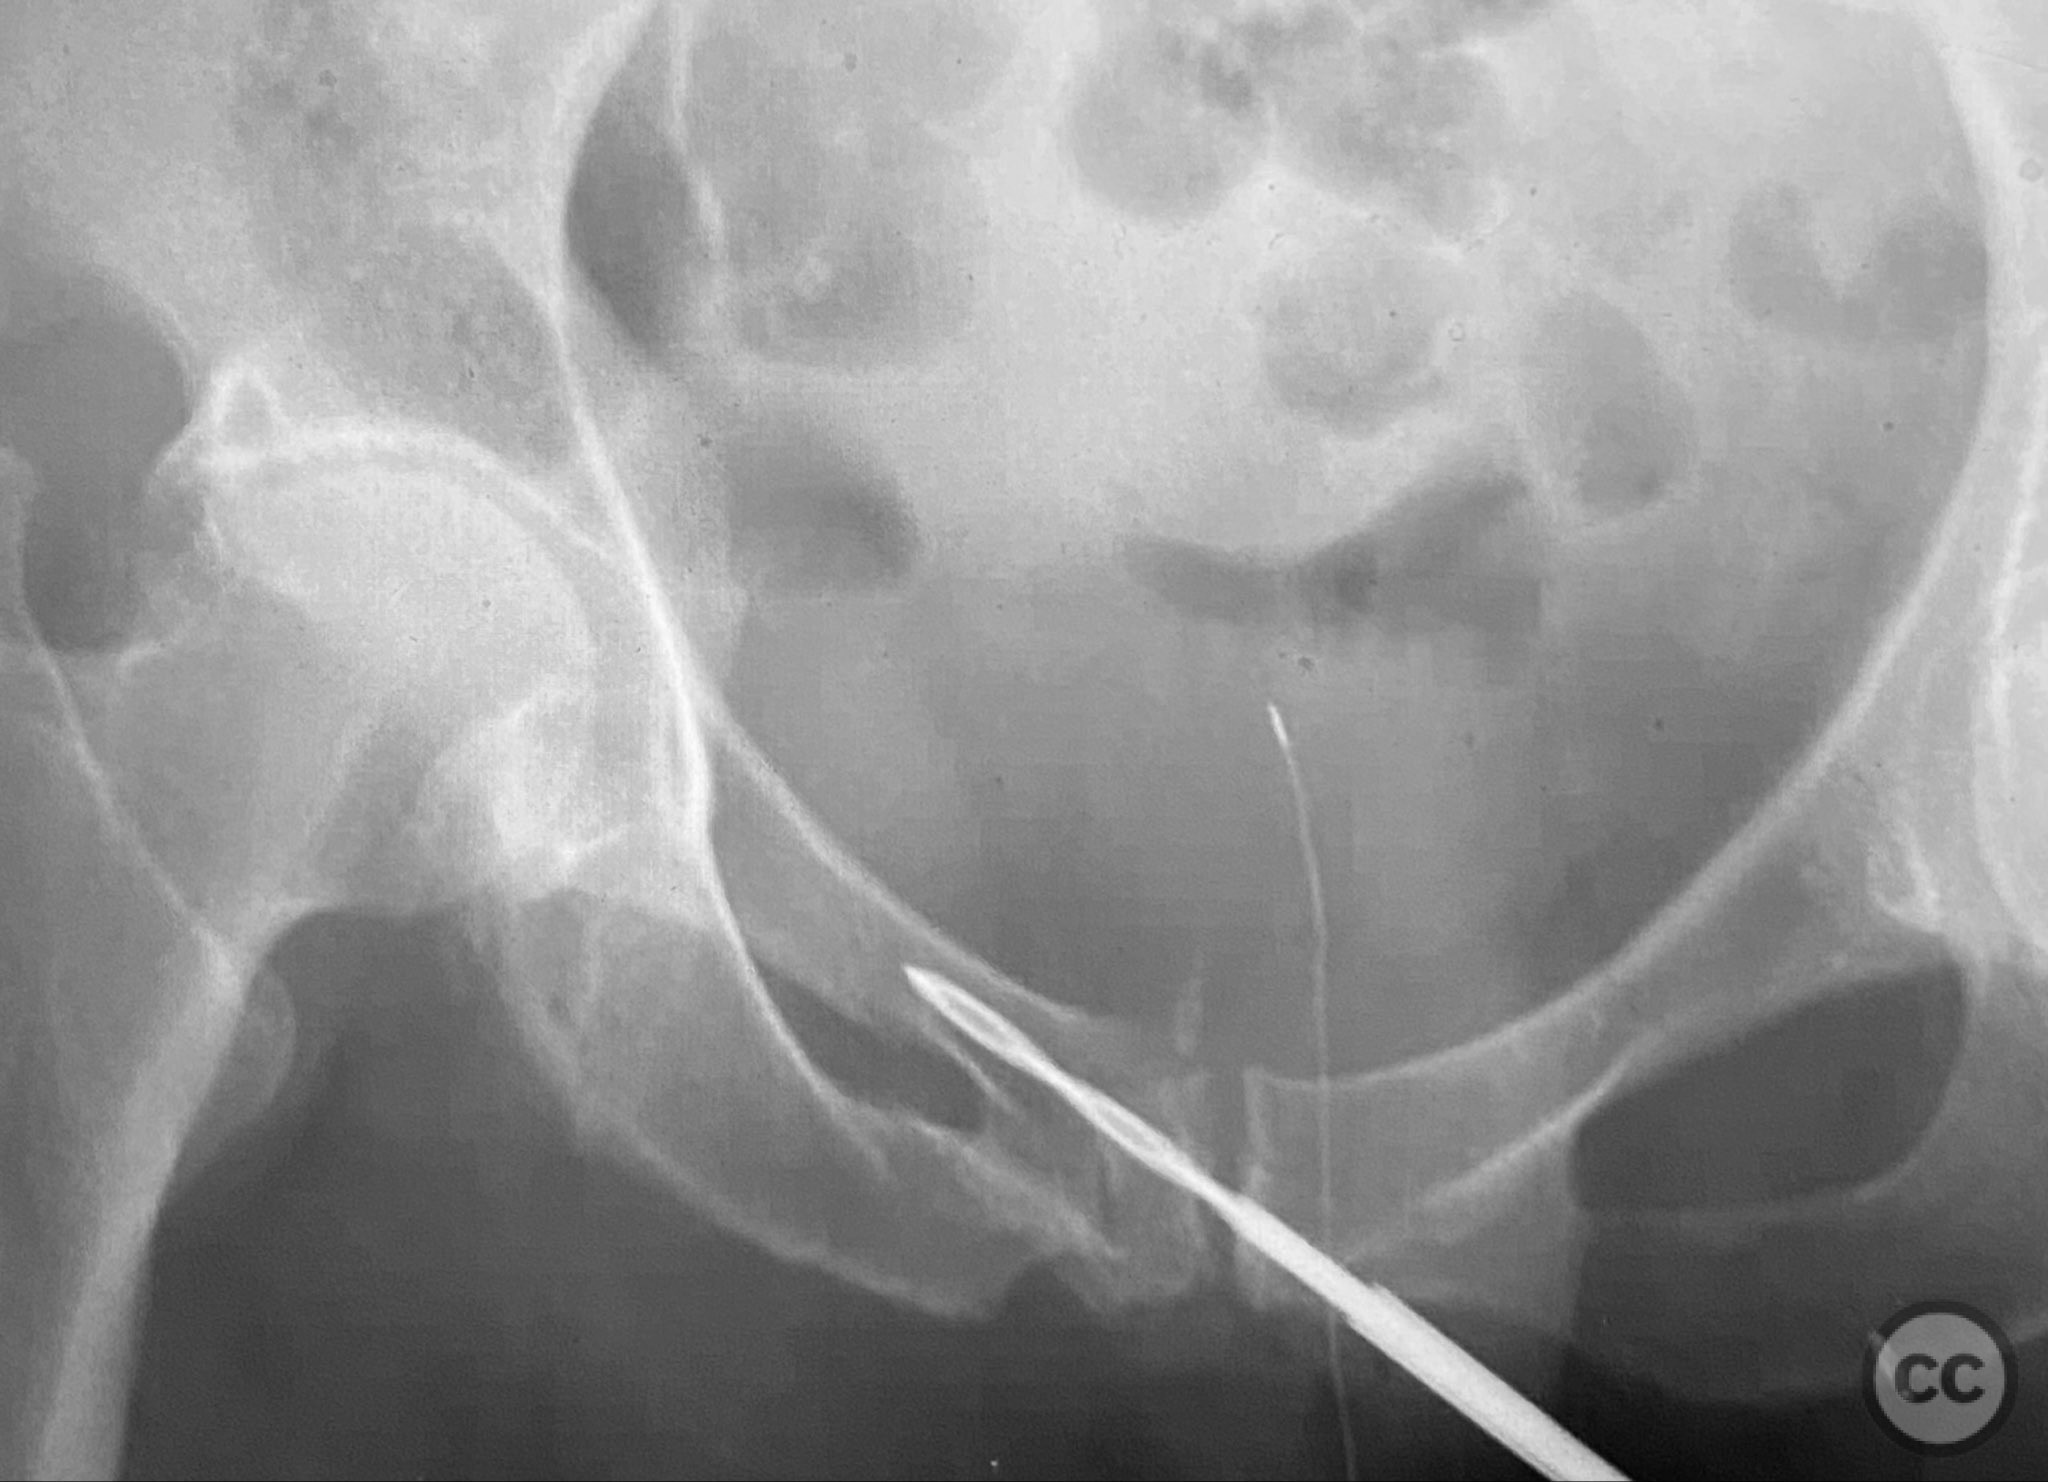

Clinical and radiological findings:  Adult patient presenting with severe pelvic pain, unable to sit or transfer to a chair. Clinical examination under anesthesia demonstrated pelvic instability with “rebound reduction” upon minimal iliac crest compression. Imaging revealed an unstable superior pubic ramus fracture with challenging anterior pelvic bone anatomy and dense cortical bone at the anterior acetabular wall.

Planning remarks:  Planned trans-symphyseal fixation of the superior pubic ramus fracture using a 4.5mm cortical screw, with preoperative intent to maximize implant purchase in stable bone regions. Surgical approach selected to facilitate direct access to the superior pubic ramus and symphysis pubis.

Intraoperatively, a 3.5mm drill was used through a protective sleeve to initiate the screw pathway across the superior pubic ramus. Due to poor bone quality, a 2.5mm drill was subsequently employed; however, resistance was encountered as the drill tip engaged the dense cortical apex of the anterior acetabular wall. The drill became lodged in this region. To avoid drill breakage, manual extraction using pliers was considered; however, the surgeon elected to carefully deflect and advance the drill manually, successfully completing the pathway. Screw length was measured directly from the embedded drill tip. A 4.5mm cortical screw was then inserted trans-symphyseally along the prepared medullary canal, achieving stabilization of the unstable ramus fracture. Postoperative CT confirmed appropriate screw trajectory and demonstrated the dense cortical bone at the anterior acetabular wall where the drill tip had engaged.